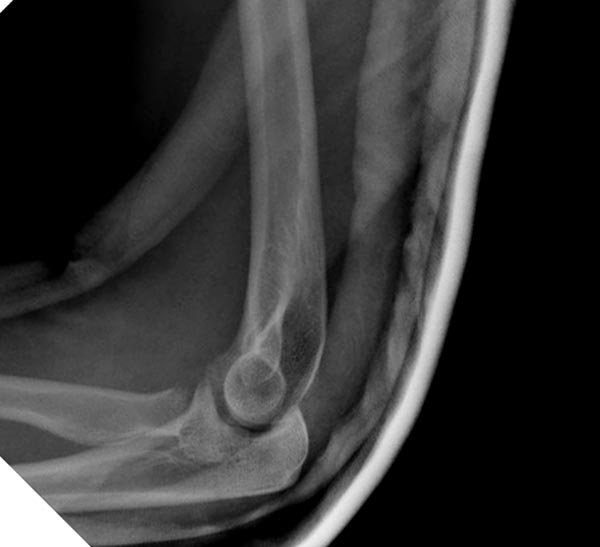

[Ortho] ПЕРЕЛОМ ГОЛОВКИ ЛУЧЕВОЙ КОСТИ.

Второе наблюдение

Имя     : 1 Elbow radial head fx.jpg

Тип     : image/jpeg